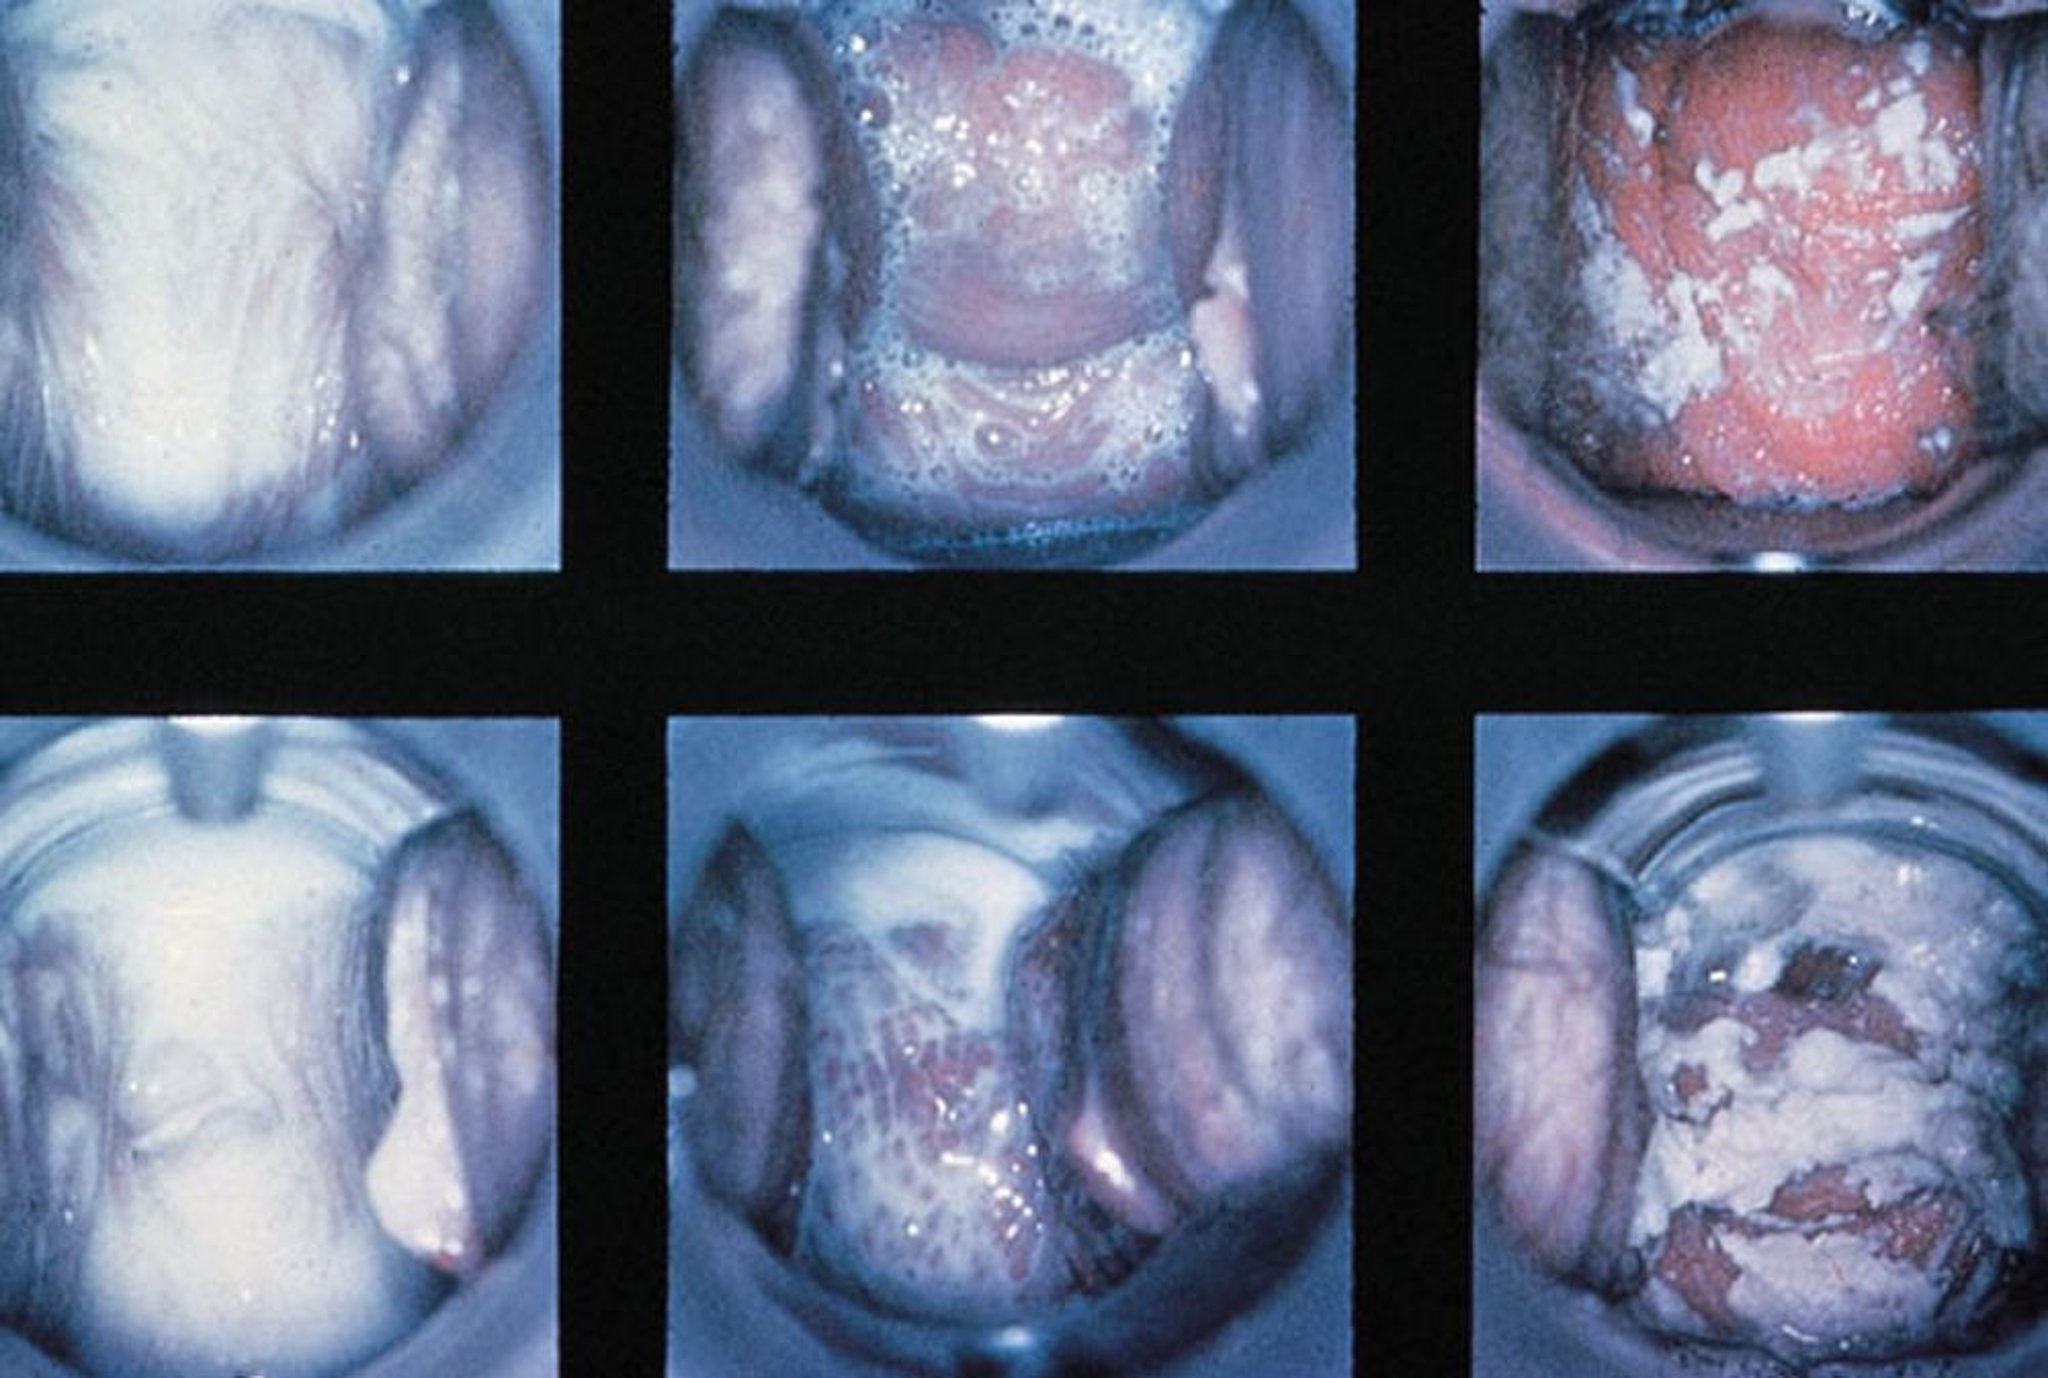

Esame con lo speculum in caso di vaginite

Vengono mostrati reperti normali, di vaginite tricomonale con secrezioni schiumose e di vaginite da Candida con secrezioni dense e bianche (da sinistra a destra).

By permission of the publisher. From Spitzer M, Mann M. In Atlas of Clinical Gynecology: Gynecologic Pathology. Edited by M Stenchever (series editor) and B Goff. Philadelphia, Current Medicine, 1998. (Courtesy of the International Society for the Study of Vulvar Disease, from the collection of the late Dr. Herman Gardner.)